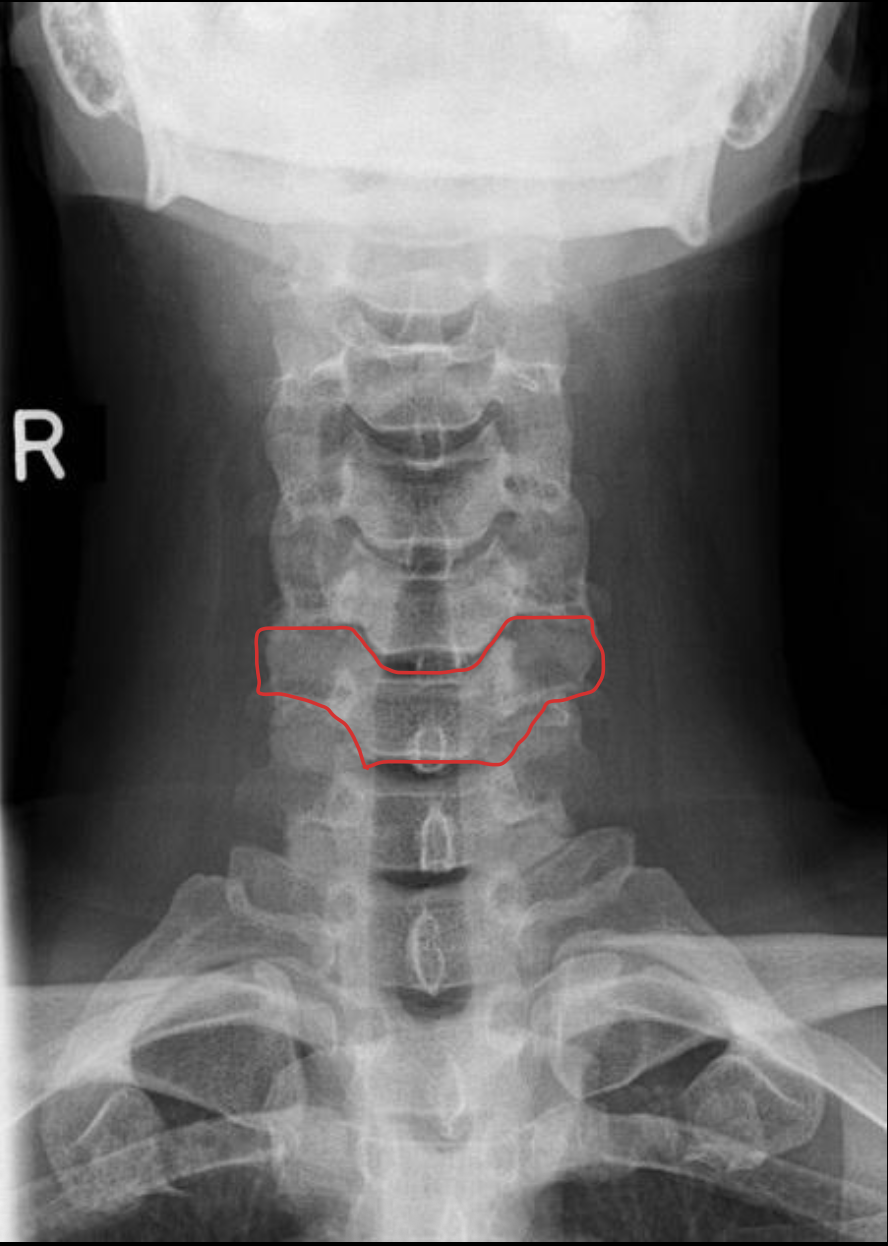

钩突

Uncinate process

关节柱 / 侧块

Articular pillars

棘突

Spinous process

椎间隙(Intervertebral Disc space)

IVD space

齿状突

Odontoid process C1

C2